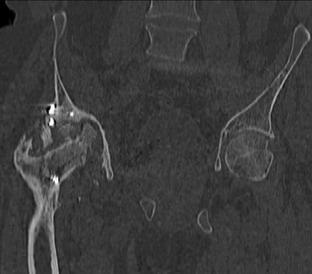

Пациент 49 лет, паровозная травма 23.2.2006, получил вертикальная

нестабильное повреждение таза, разрыв левого крестцово-подвздошного

сочленения, перелом лонной, седалищной костей слева, T-образный

оскольчатый перелом правой вертлужной впадины с переломом заднего

края, вывих правого бедра, посттравматическая пояснично-крестцовая

плексопатия с обеих сторон, паралич мышц правой голени.

В день травмы - вправление вывиха, скелетное вытяжение, 14.3.2006

чрескостный остеосинтез таза. 20.4.2006 остеосинтез правой вертлужной

впадины пластинами, осложнившийся нагноением межмышечной гематомы

правой ягодичной области. Получал консервативное лечение, было

достигнуто полное заживление раны. 24.7.2006 введены илиосакральные

винты слева. С декабря 2006 года и по настоящее время ходит на

костылях без опоры на правую ногу. Планируется THA. Помогите

определиться с вариантом костной пластики? И какую укрепляющую

конструкцию использовать?